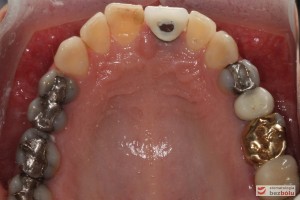

Do naszej placówki zgłosiła się starannie planująca swoje działania Europejka, mieszkająca na stałe w Kotlinie Jeleniogórskiej. Jej oczekiwania dotyczyły bardzo metodycznie zaplanowanego planu leczenia. Celem jaki postawiła przed naszym zespołem lekarzy było wyeliminowanie wszystkich wątpliwych i nierokujących wypełnień, a także poprawa estetyki w zakresie lewego siekacza centralnego w szczęce. Został rozpisany blisko dwuletni plan wymiany zużytych i nieszczelnych wypełnień amalgamatowych i kompozytowych. Zaplanowano również przygotowanie endodontyczne wybranych zębów w szczęce i żuchwie, a także zaopatrzenie w inlay’e porcelanowe i korony ceramiczne wykonane w systemie e-max.